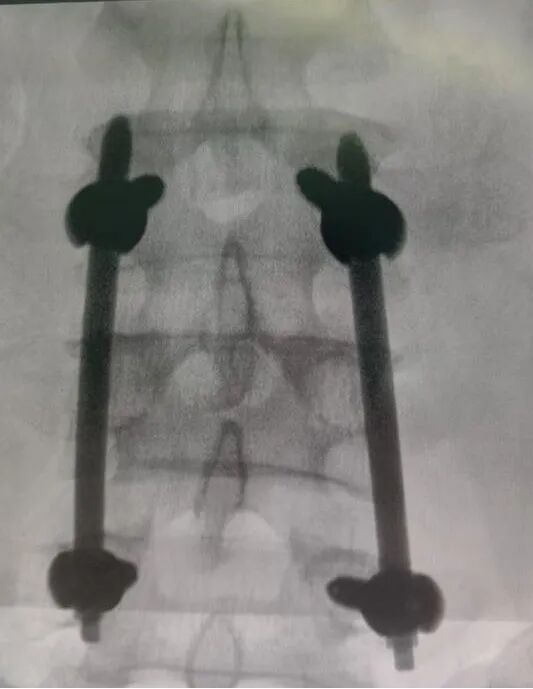

患者江先生,56岁,因外伤4椎体压缩性骨折。为了最大限度减少对患者的创伤,加快其康复,术前科室进行认真讨论,查阅资料,观看手术视频,制订详细的手术计划,于929日在全麻下行微创小切口脊柱后路钉棒系统内固定术治疗腰4椎体压缩性骨折,术后复查X线提示腰椎高度恢复,内固定位置正常。

姚主任介绍道,传统椎弓根内固定植骨融合术采用切开皮肤,剥离肌肉,显露椎体结构后,植入椎弓根螺钉固定,存在创伤大(约10厘米)、椎旁肌肉剥离广泛、术中出血多(一般出血约300毫升)、术后切口引流量大(一般约200毫升)、术后切口疼痛、恢复期长等。而微创经皮椎弓根钉棒内固定植骨融合术因其手术创伤小(约2厘米),术中出血少(约20毫升),不剥离椎旁肌肉,术后切口无需引流,无术后切口疼痛,可早期下地进行功能恢复,是近年来发展起来的新技术,也是目前微创治疗腰椎滑脱、胸腰椎骨折、椎管狭窄、肿瘤等脊柱疾病的一种先进手术方式。经皮椎弓根钉棒系统内固定术微创技术,对手术技术要求比传统手术方式更高,术前需要非常周密的计划,根据患者的影像资料做非常精确地测量和定位,更需要手术医生具有非常娴熟的开放椎弓根钉棒系统内固定技术及经皮椎弓根穿刺技术。